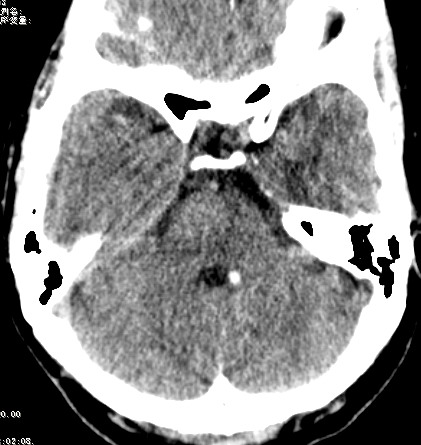

女,46岁,头晕1周。(第四脑室点状高密度灶,ct值约为65hu)。

四脑室脉络从钙化。

第四脑室脉络丛钙化。